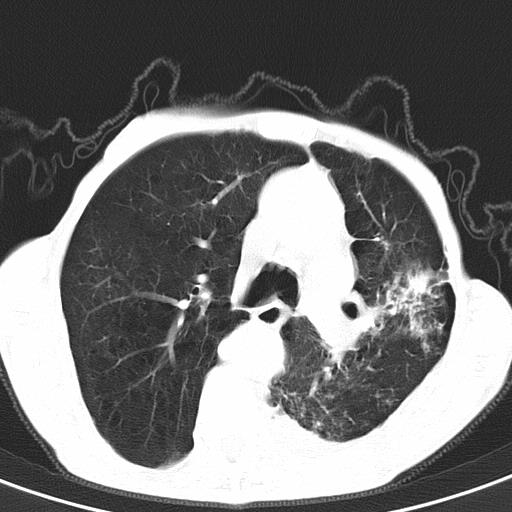

患者78岁,咳嗽胸闷一年余,近月来左侧胸痛;

建议强化,首先考虑左肺癌胸膜转移。

患者左侧胸廓塌陷说明是长期病变,考虑tb性胸膜炎可能性大,另外有明显的肺气肿,建议行结核菌素实验,或者增强扫描

1.慢支肺气肿。2.左肺感染,建议治疗后复查。3.左侧少量胸水。

1.慢支肺气肿。2.左肺感染,建议治疗后复查,待除外继发性肺结核合并感染。3.左侧少量胸水。

1)考虑左肺慢性感染性病变(结核可能)。2)左肺上叶周围型肺癌不排除;建议追踪复查。3)肺气肿。4)左侧胸腔积液,左侧胸膜增厚、粘连。